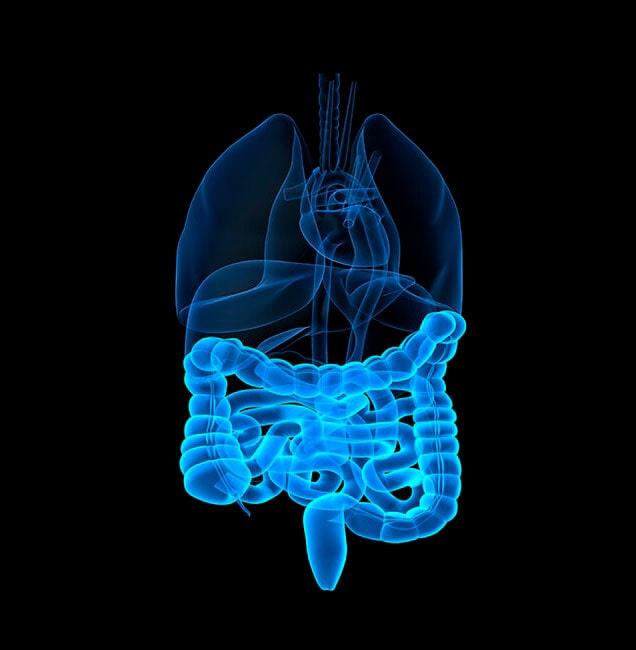

¿Buscas un proctólogo especialista en Los Mochis, Sinaloa? Encuentra con el Dr. Waskar Eliezer Ynzunza Vega, coloproctólogo, la ayuda profesional que requieres en medicina privada, para la atención eficaz de enfermedades del colon, recto y ano.

Cuenta con amplia experiencia en cirugía colorrectal y en proctología en general, para tratar problemas de hemorroides, estreñimiento, colitis, abscesos, fístulas, infecciones anorrectales, entre otros.

¿Buscas un proctólogo especialista en Los Mochis, Sinaloa? Encuentra con el Dr. Waskar Eliezer Ynzunza Vega, coloproctólogo, la ayuda profesional que requieres en medicina privada, para la atención eficaz de enfermedades del colon, recto y ano.

Cuenta con amplia experiencia en cirugía colorrectal y en proctología en general, para tratar problemas de hemorroides, estreñimiento, colitis, abscesos, fístulas, infecciones anorrectales, entre otros.